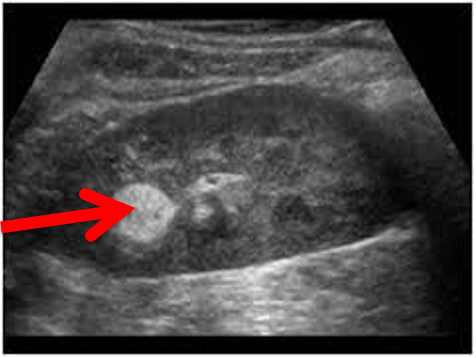

The area indicated by the red arrow can be described as __________ which indicates that there are ___________ reflected signals.

hyperechoic, highly

This gallstone demonstrates what 2 main types of attenuation?

Absorption and reflection